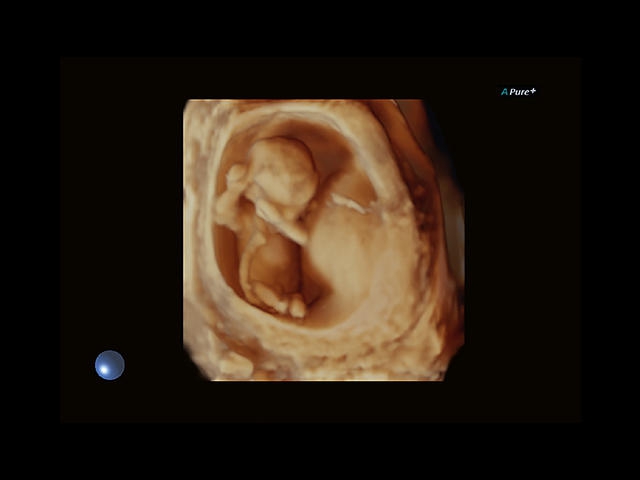

Aplio 500 – ультразвуковой сканер премиум класса, сочетающий в себе быстродействие диагностики и отличное качество визуализации. Более 30 датчиков на выбор, в т.ч. матричные, монокристаллические, 4D, эндоскопические для любых типов исследований. Ультразвуковой сканер позволяет изучать анатомические структуры в высоком разрешении.

Обновленная версия легендарного УЗ-сканера. Стационарный аппарат экспертного класса Aplio 500 Toshiba NEW, визуализирует анатомические структуры в высоком разрешении. Модель позволяет выявить микрокальцификаты, новообразования, нарушения в работе сердца, сосудов и мышц. Присутствует функция виртуальной эндоскопии, 4D-сканирования, эластометрии тканей, УЗИ с контрастированием. За повышение качества изображения отвечают технологии ApliPure и Superb Microvascular Imaging. Первая задействует возможности пространственного и частотного кодирования, формирует цельный визуальный ряд с сохранением клинических маркеров. Вторая улучшает отображение микрососудистого русла, используя доплеровский эффект. Модель оснащена 21-дюймовым монитором, имеет 4 активных порта. Возможно подключение педиатрических, интраоперационных, лапароскопических и чреспищеводных датчиков.

Общая визуализация, Гинекология и акушерство, УЗИ для кардиологии

4D:

STIC: